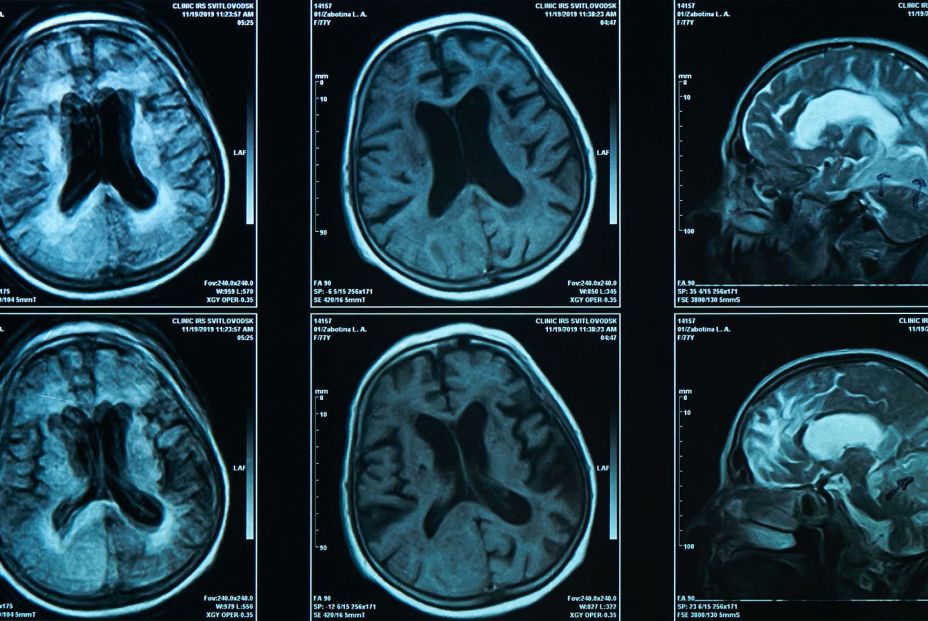

Pues ahora llega una nueva investigación, publicada en 'Jama Cardiology', que constata que el empleo de sustitutos de la sal reducen el riesgo de recurrencia del ictus y muerte por su causa,

Los autores del estudio descubrieron que la sustitución de la sal era segura y conducía a una reducción del 12% en la mortalidad y una reducción del 14% en el riesgo de accidente cerebrovascular recurrente.

Los investigadores descubrieron que entre los del grupo de sustitutos de la sal, las tasas de accidente cerebrovascular recurrente fueron significativamente más bajas en comparación con el grupo de sal común. Y las de ictus recurrente fueron particularmente más bajas en el caso de los accidentes cerebrovasculares hemorrágicos. Las tasas de mortalidad también fueron más bajas en el grupo que tenía sustitutos de la sal.